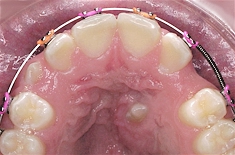

In this case, an ectopic canine (eye tooth) was surgically exposed and braces were used to move it into its correct position.